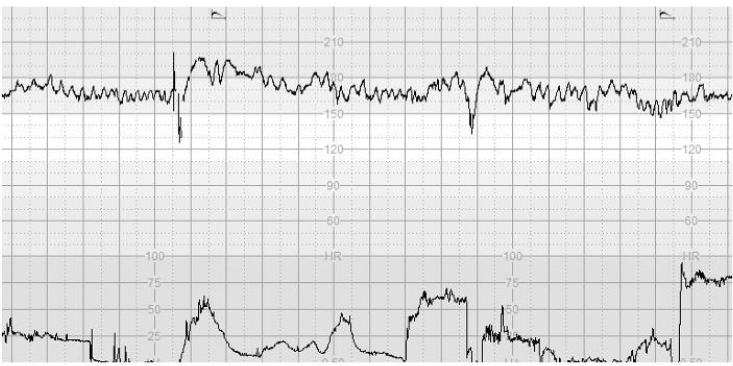

Figure 1 illustrates >10% increase in the baseline FHR without repetitive decelerations, absence of cycling and presence of the “Poole Shark Teeth Pattern” six hours after spontaneous rupture of membranes.

Figure 1. CTG trace illustrates >10% increase in the baseline FHR without repetitive decelerations, absence of cycling and presence of the “Poole Shark Teeth Pattern”, which are the features of SOFI, following SROM.